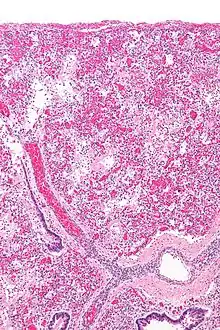

تُعد متلازمة الضائقة التنفسية الحادة شكل من أشكال الوذمة الرؤوية التي لا يمكن تفسيرها بفشل القلب (ولذا تُسمى بالوذمة الرؤوية غير القلبية)، وتحدث هذا المتلازمة بسبب مرض حاد في الرئتين، مايؤدي إلى إغراق الحويصلات الهوائية المسؤولة عن تبادل الغازات (الأكسجين وثاني أكسيد الكربون) مع الشعيرات الدموية في الرئتين.[10] وترتبط المتلازمة بنتائج مرضية قد تشمل الالتهاب الرئوي، والالتهاب الرئوي الالتهاب الرئوي اليوزيني، التهاب القصيبات المسد لذات الرئة المنظم، التأذي السنخي المنتشر، والذي يتميز بالتهاب منتشر في أنسجة الرئة، وعادةً ما ينتج عن تهييج المرض لأنسجة الرئة إطلاق للسيتوكينات وغيرها من دلالات الالتهاب الأخرى التي تُفرزها خلايا النسيج الطلائي والبطانية الغشائية. تهاجر الخلايا المتعادلة وبعض الخلايا اللمفاوية بسرعة إلى أنسجة الرئة الملتهبة، ويظهر في النسيج -بشكل نموذجي- انتشار تأذي الحويصلات وتشكيل الغشاء الزجاجي (الهيالين) في جدرانها.